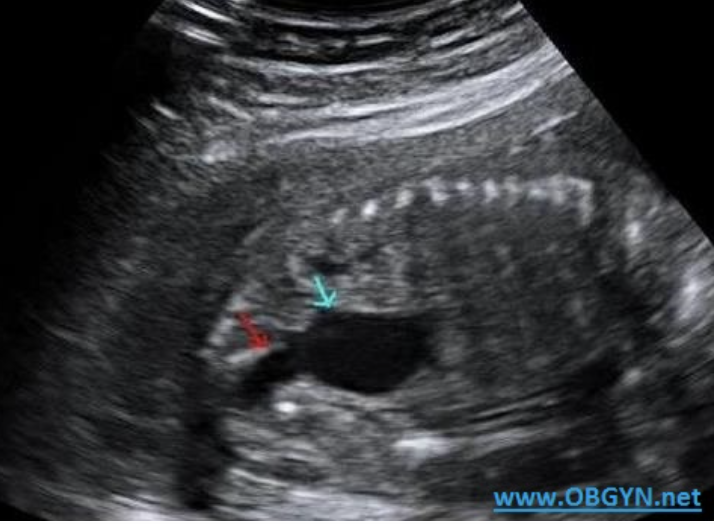

a) dilated urinary bladder

b) cystic hygroma

c) double bubble

d) normal fetal abd/pelvis